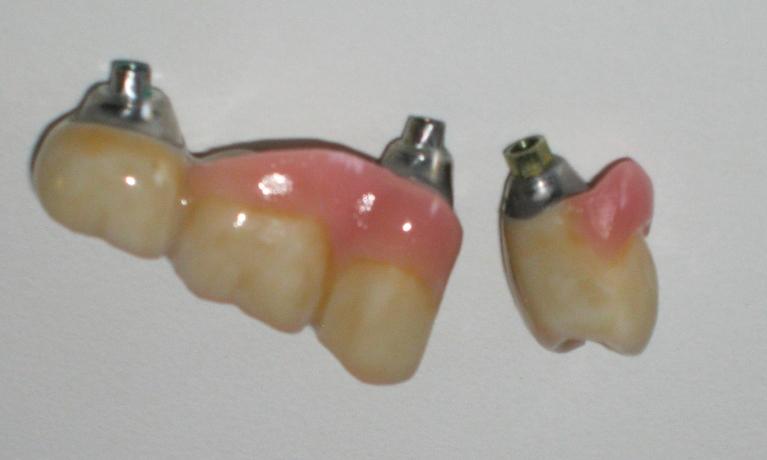

We take great pride in the services we perform in our office. We always try to not only meet your expectations, but we also try to exceed them. There are many types of services that we perform in our office, as well as others that we perform in coordination with highly skilled specialists. We have compiled a few examples of the treatments that we have performed. We are proud to say that these are the usual results our patients expect to see.

The photos are not retouched, nor are they taken by a professional photographer. These are just the routine treatment photos that we take and the results that we see every day. They are by no means a comprehensive catalog of the procedures that we perform. They are just a small sample of some of the results you can expect when you seek treatment in our office.